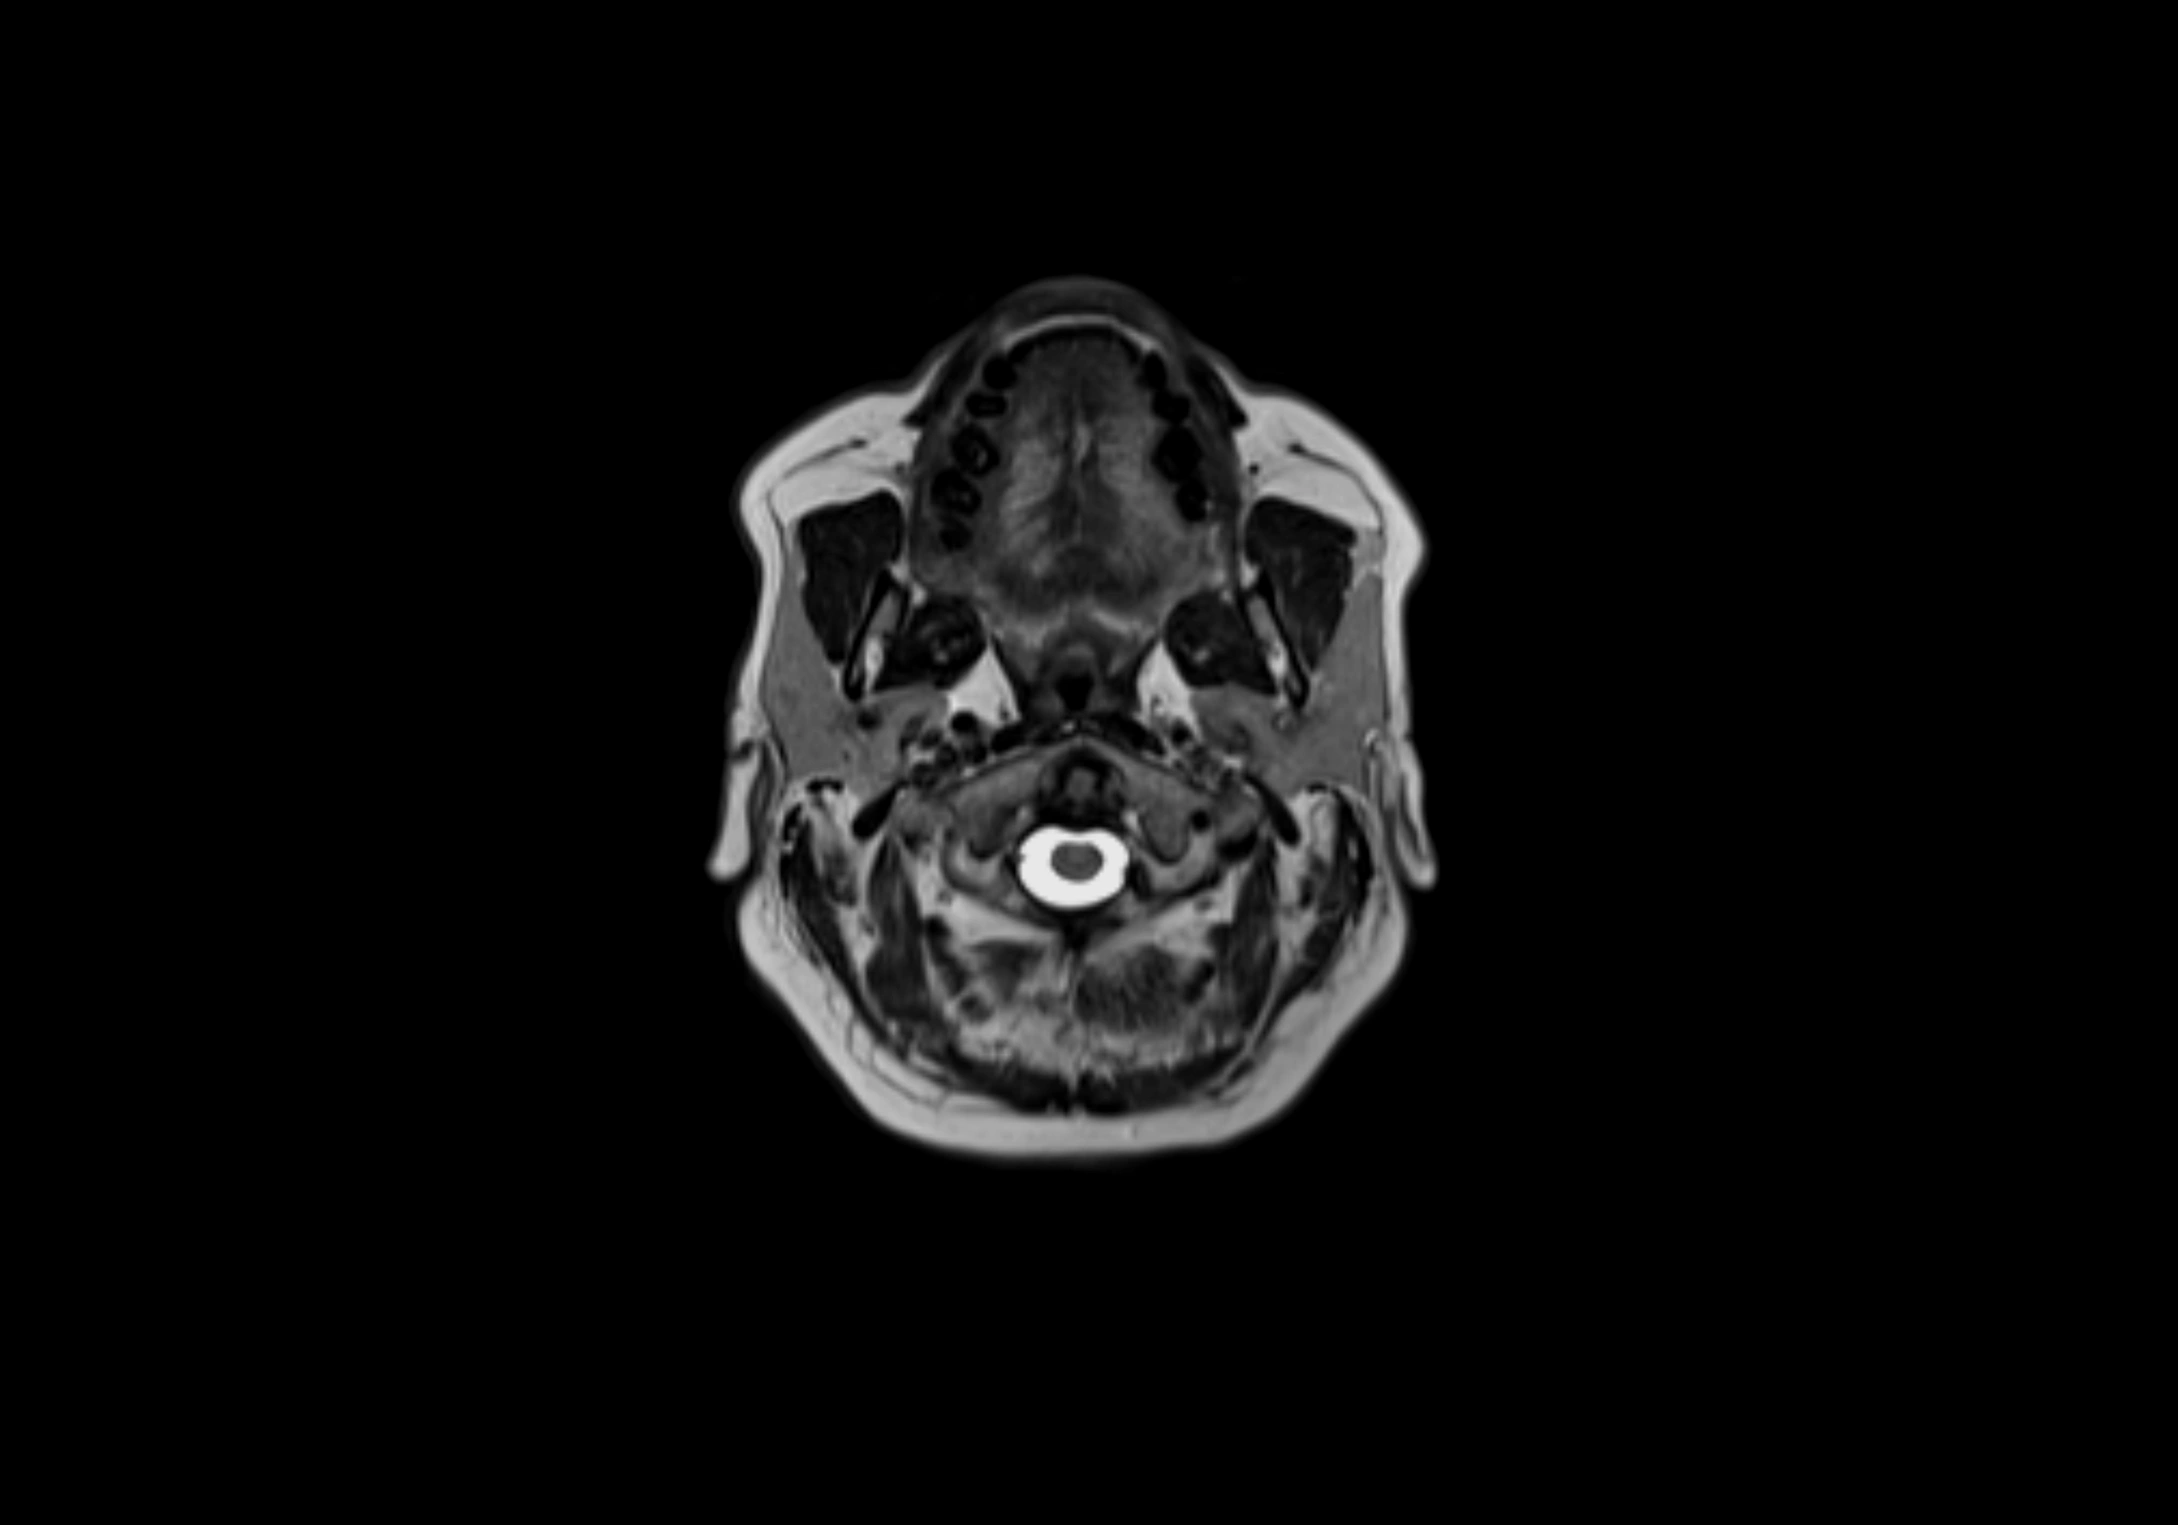

MRI Appearance

T1-weighted images:

• Normal accessory nodes appear as small, oval hypointense to intermediate signal structures within subcutaneous fat

• Surrounded by hyperintense fat, enhancing contrast for visualization

T2-weighted images:

• Nodes show intermediate signal, with surrounding fat bright

• Useful for detecting edema, inflammation, or infiltration

• Fatty hilum may appear slightly hyperintense relative to cortex